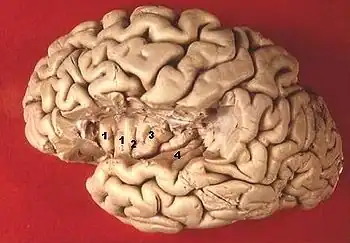

| Coupe coronale | Vue de la face supérieure de T1 et de l'insula après résection d'une partie du lobe frontal et pariétal 1,2,3 : gyrus de l'insula 4 gyrus temporal transverse |

Le gyrus temporal supérieur T1 est un gyrus du lobe temporal du cortex cérébral. Il comporte deux parties :

- la face supérieure, pénétrant dans la profondeur de la scissure de Sylvius, non visible latéralement car recouverte par les lobes frontal et pariétal. Cette région s'enfonce profondément dans le cerveau jusqu'à l'insula. Elle est divisée en

- planum polare, en avant vers le pôle temporal,

- gyrus temporal transverse ou gyrus de Heschl, sous l'opercule central,

- planum temporale, plus en arrière ;

- la face latérale, est la partie visible latéralement, s'étendant vers le bas jusqu'au sillon temporal supérieur. D'avant en arrière, elle couvre une bande allant du pôle temporal, en avant, jusqu'à une ligne non anatomique, partant du point de verticalisation de la scissure de Sylvius, et la séparant du lobule pariétal inférieur.